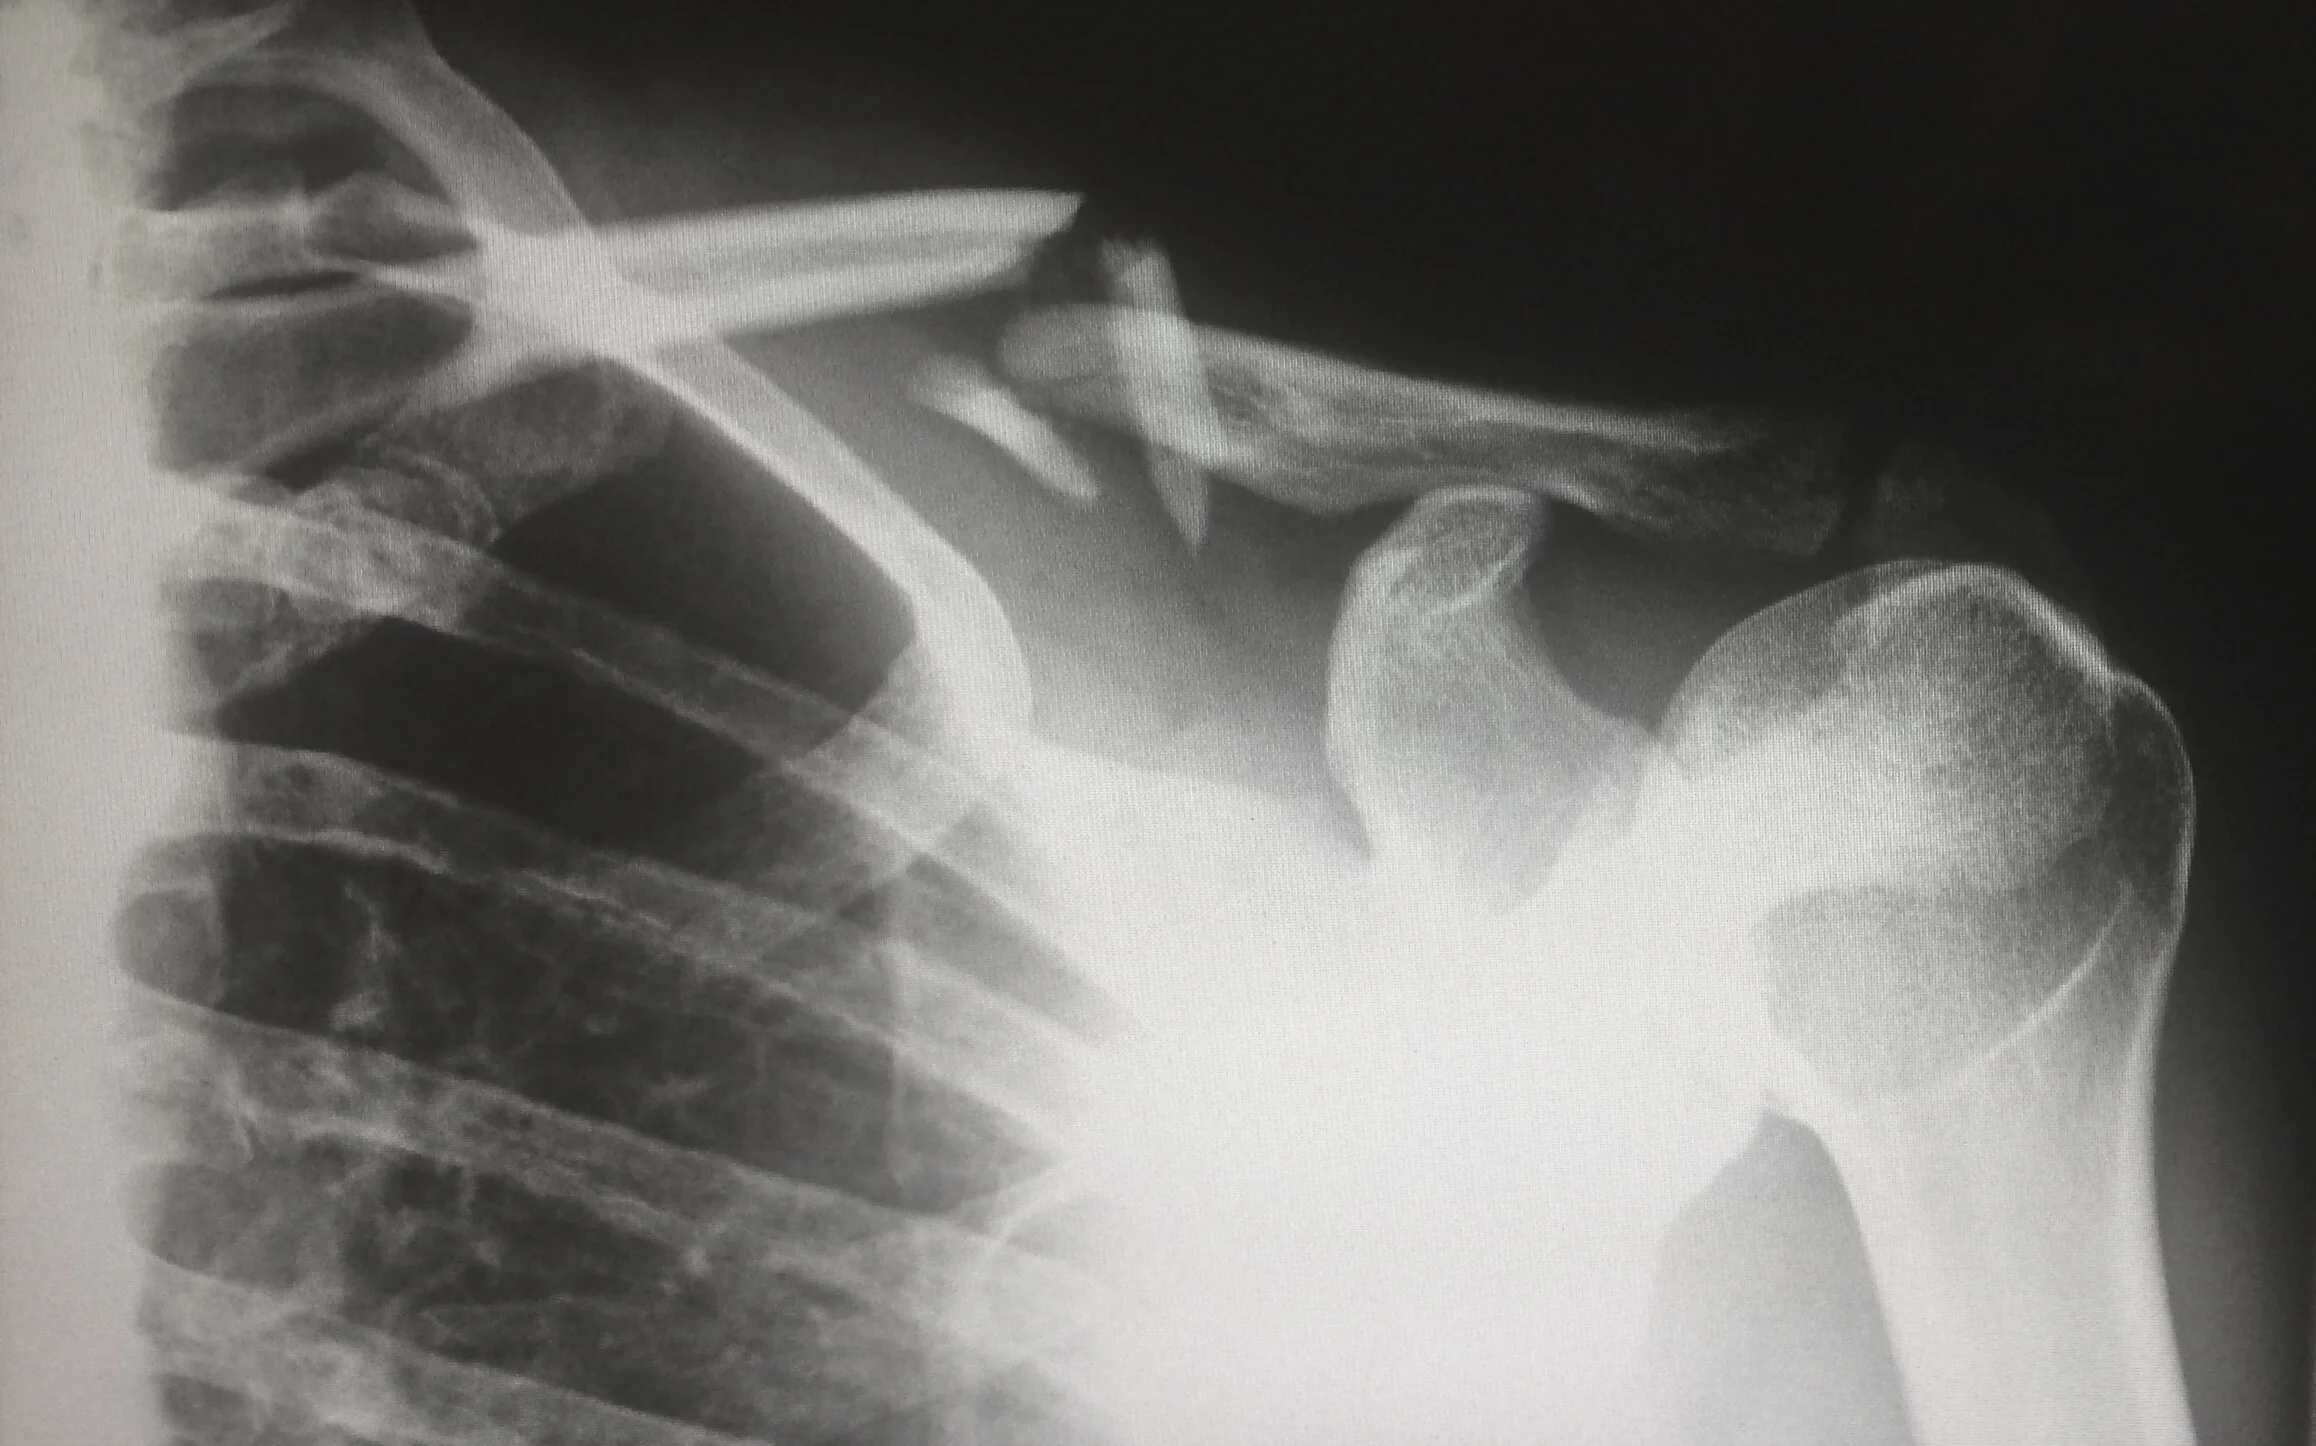

• Detection of fractures in potential child abuse

Using techniques that include the production and analysis of X-Rays, CT Scans, and MRI scans, our Radiologists and Neuro-radiologists will be able to address any questions posed by your case.